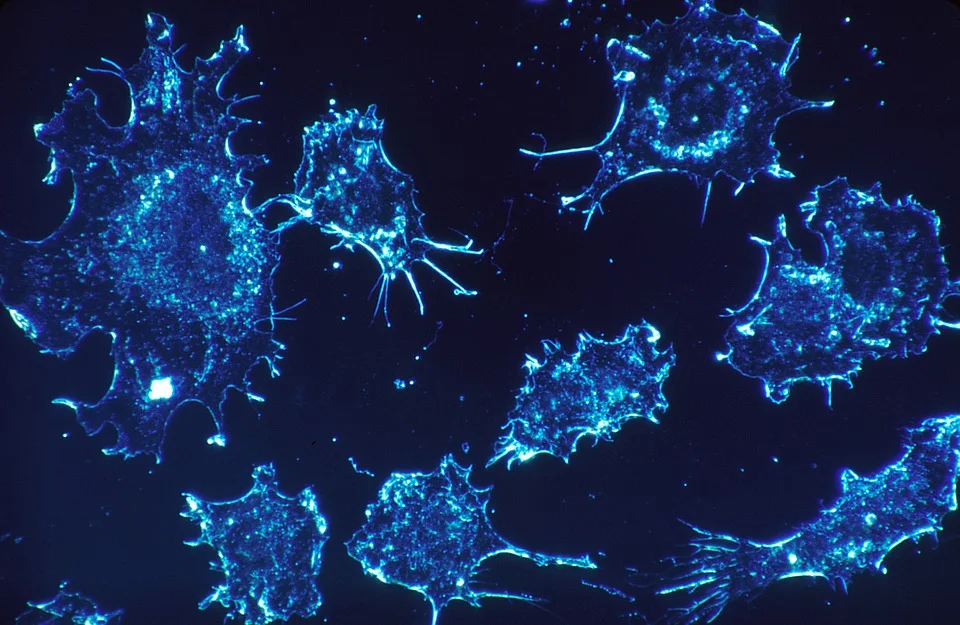

49. Cancer

Cannabinoids possess anti-proliferative and pro-apoptotic effects and they are known to interfere with tumour neovascularization, cancer cell migration, adhesion, invasion and metastasization. R RRRR

Cannabinoids have major potential in cancer:

- CBD is able to produce antitumor activity both in vitro and in vivo. R

- It is able to limit tumor invasion. R

- It inhibits the invasion of glioblastoma cells in vivo. R R

- Combined with a TRPV2 agonist, CBD increases drug uptake while potentiating cytotoxic activity in brain cancer cells. R

- Cannabinoid-loaded microparticles enhanced cell death and decreased cell proliferation and angiogenesis in brain cancer cells. R

- Of the 5 natural compounds tested, CBD is the most potent inhibitor of breast cancer cell growth. R

- CBD increased the generation of reactive oxygen species (ROS), and ROS inhibition blocked the induction of apoptosis and autophagy. R

- It down-regulated Id-1 gene expression in aggressive human breast cancer cells in culture. R

- In colorectal carcinoma cell lines, CBD protected DNA from oxidative damage, and reduced cell proliferation. R

- CBD-induced apoptosis was CB1 and CB2 receptor-dependent. R

- CBD induces apoptosis in human leukemia cells. R

- CBD treatment led to a significant decrease in tumor burden and an increase in apoptotic tumors in vivo. R

- CBD inhibits lung cancer cell invasion and metastasis (via ICAM1). R

- It also induces PRAR-γ-dependent apoptotic cell death in human lung cells. R